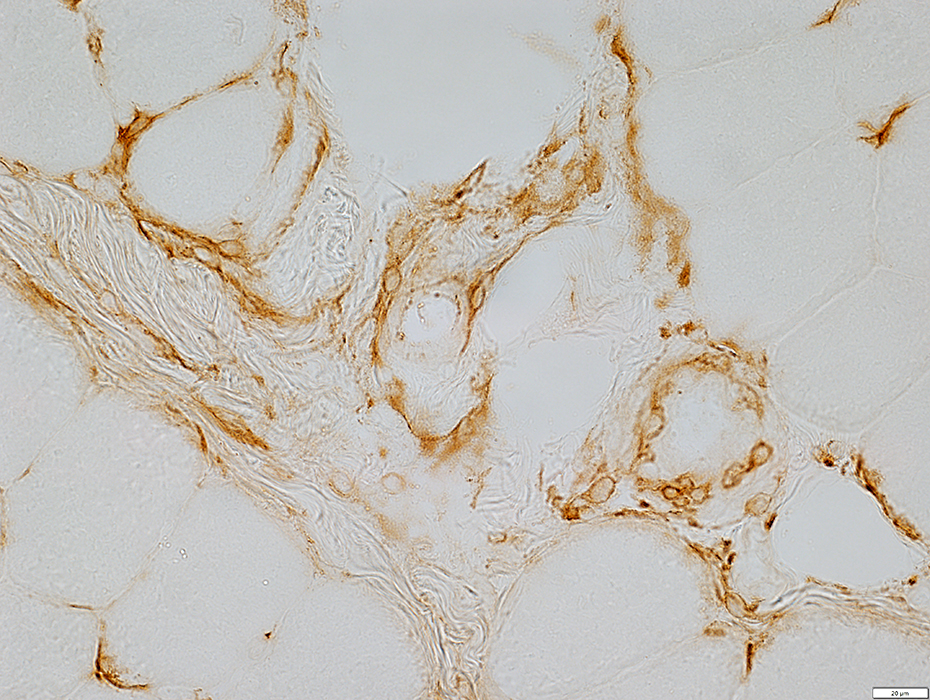

MHC Class I stain

MHC Class I

Mildly increased on muscle fiber surfaces

muscle Fibers

MHC Class I stains cells in & around vessel walls